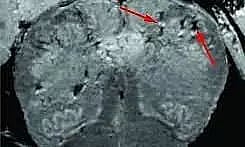

NEW DELHI: Patients who had recovered from mild or moderate SARS-CoV-2 infection were seen to have suffered some loss of grey matter in the areas that govern cognitive skills, memory-making, sensory functions like smell and taste.

A study in the UK looked into the long-term impact of the novel coronavirus infection on the human brain, post-recovery - and has made some findings using before-after images of brain scans of COVID-19 recovered patients has made a stunning discovery.